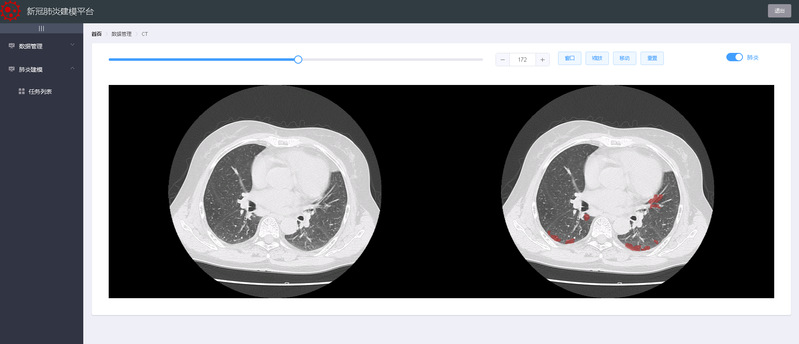

近日,由乐天使感知计算研究中心王宽全教授团队研发出“新冠肺炎在线建模平台”软件,现已部署到云平台并投入应用。该系统率先将人工智能技术、云计算技术和计算机图形学综合应用于临床胸部CT图像分析,不仅能实现全天候24小时不间断服务,打破传统医学分析软件部署应用过程中时间和空间的限制,同时能够在2分钟之内实现全自动识别肺部新冠肺炎病灶区域,在辅助医生临床诊断新冠肺炎患者病情方面发挥了重要作用。

CT图像与肺炎区域对照